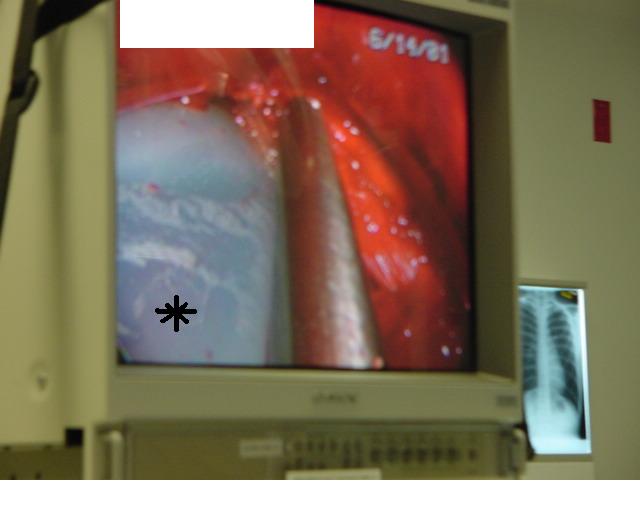

Once the tunnel reaches the sternum, the endoscopic tunneling device is utilized to visualize the clamp entering the interspace of maximal pectus depth and passing retrosternal (Figure 7). At the level of the sternum, these tunnels go retrosternal and communicate with each other. Ideally, even after entering the interspace, the tunnel stays extrapleural. The endoscopic view of the tunnel allows visualization of the safe passage of the clamp under the sternum and anterior to the pericardium. The mediastinum and pericardium can be seen pulsating posterior to the clamp. Two monitoring screens are utilized in order to allow excellent visualization by both the surgeon and assistant (Figure 8). Eventually, the larger curved clamp is easily passed under the sternum (Figure 9). This clamp is thus passed through one midaxillary skin incision and out the other midaxillary skin incision.